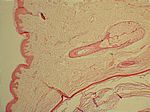

Epidermoidzyste, HE